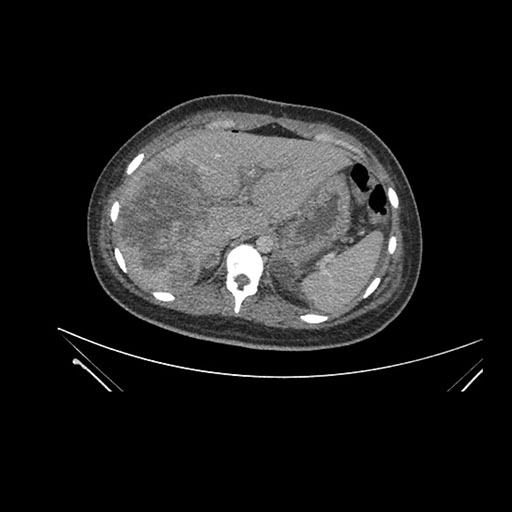

Axial Arterial

Axial Venous

Imaging analysis

Based on initial findings, which issue(s) would you be most concerned about?